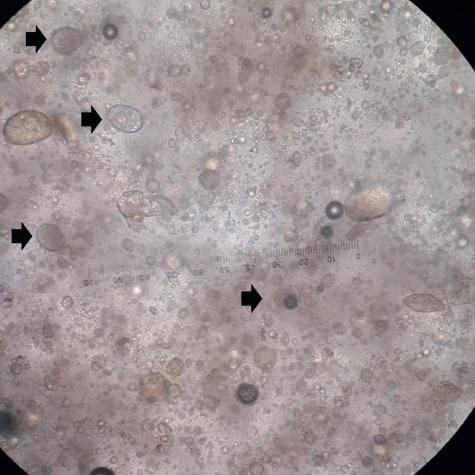

Foto’s: bemonstering en beeld van oöcysten (pijlen) en mestdeeltjes door een microscoop. Door een afschraapsel van de darm te nemen en onder de microscoop te bekijken, kan de diagnose coccidiose worden bevestigd. Aan de hand van de grootte van de oöcysten, de locatie van het monster en de afwijkingen in de darm is het mogelijk om de betrokken eimeriasoort vast te stellen. Ter bevestiging van de wat minder voorkomende eimeriasoorten is het mogelijk om een afschraapsel in te sturen voor de Coccidiose (Eimeria)-qPCR.